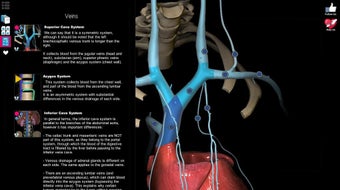

Anatomy Learning - 3D Atlas è un'app gratuita per Android che appartiene alla categoria Medicina ed è stata sviluppata da AnatomyLearning. È consigliata per principianti, studenti di medicina, apprendisti visivi, professionisti medici, medici.

Questa app è meglio conosciuta per le seguenti caratteristiche e qualità: strumento di studio, apprendimento dell'anatomia, strumento di apprendimento e riferimento di base.